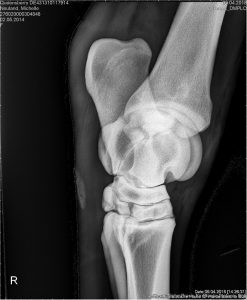

- Kniegelenke seitlich:

Darstellung von Kniescheibe, Ober- und Unterschenkelteile in seitlicher Betrachtung.

- Kniegelenke AP/ „Vorne-Hinten“ Darstellung:

Aufnahme der Kniegelenke von vorne nach hinten mit Darstellung des Gelenkspaltes.

Röntgenbild rechtes Hinterbein